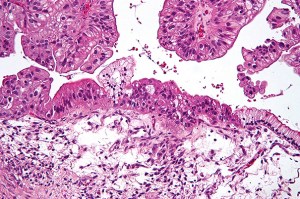

Updating embryo research guidelines

Scientists and ethicists gathered at Harvard Law School to discuss the ethics of human embryo experimentation and whether a two-week developmental time limit on their use is appropriate any longer.